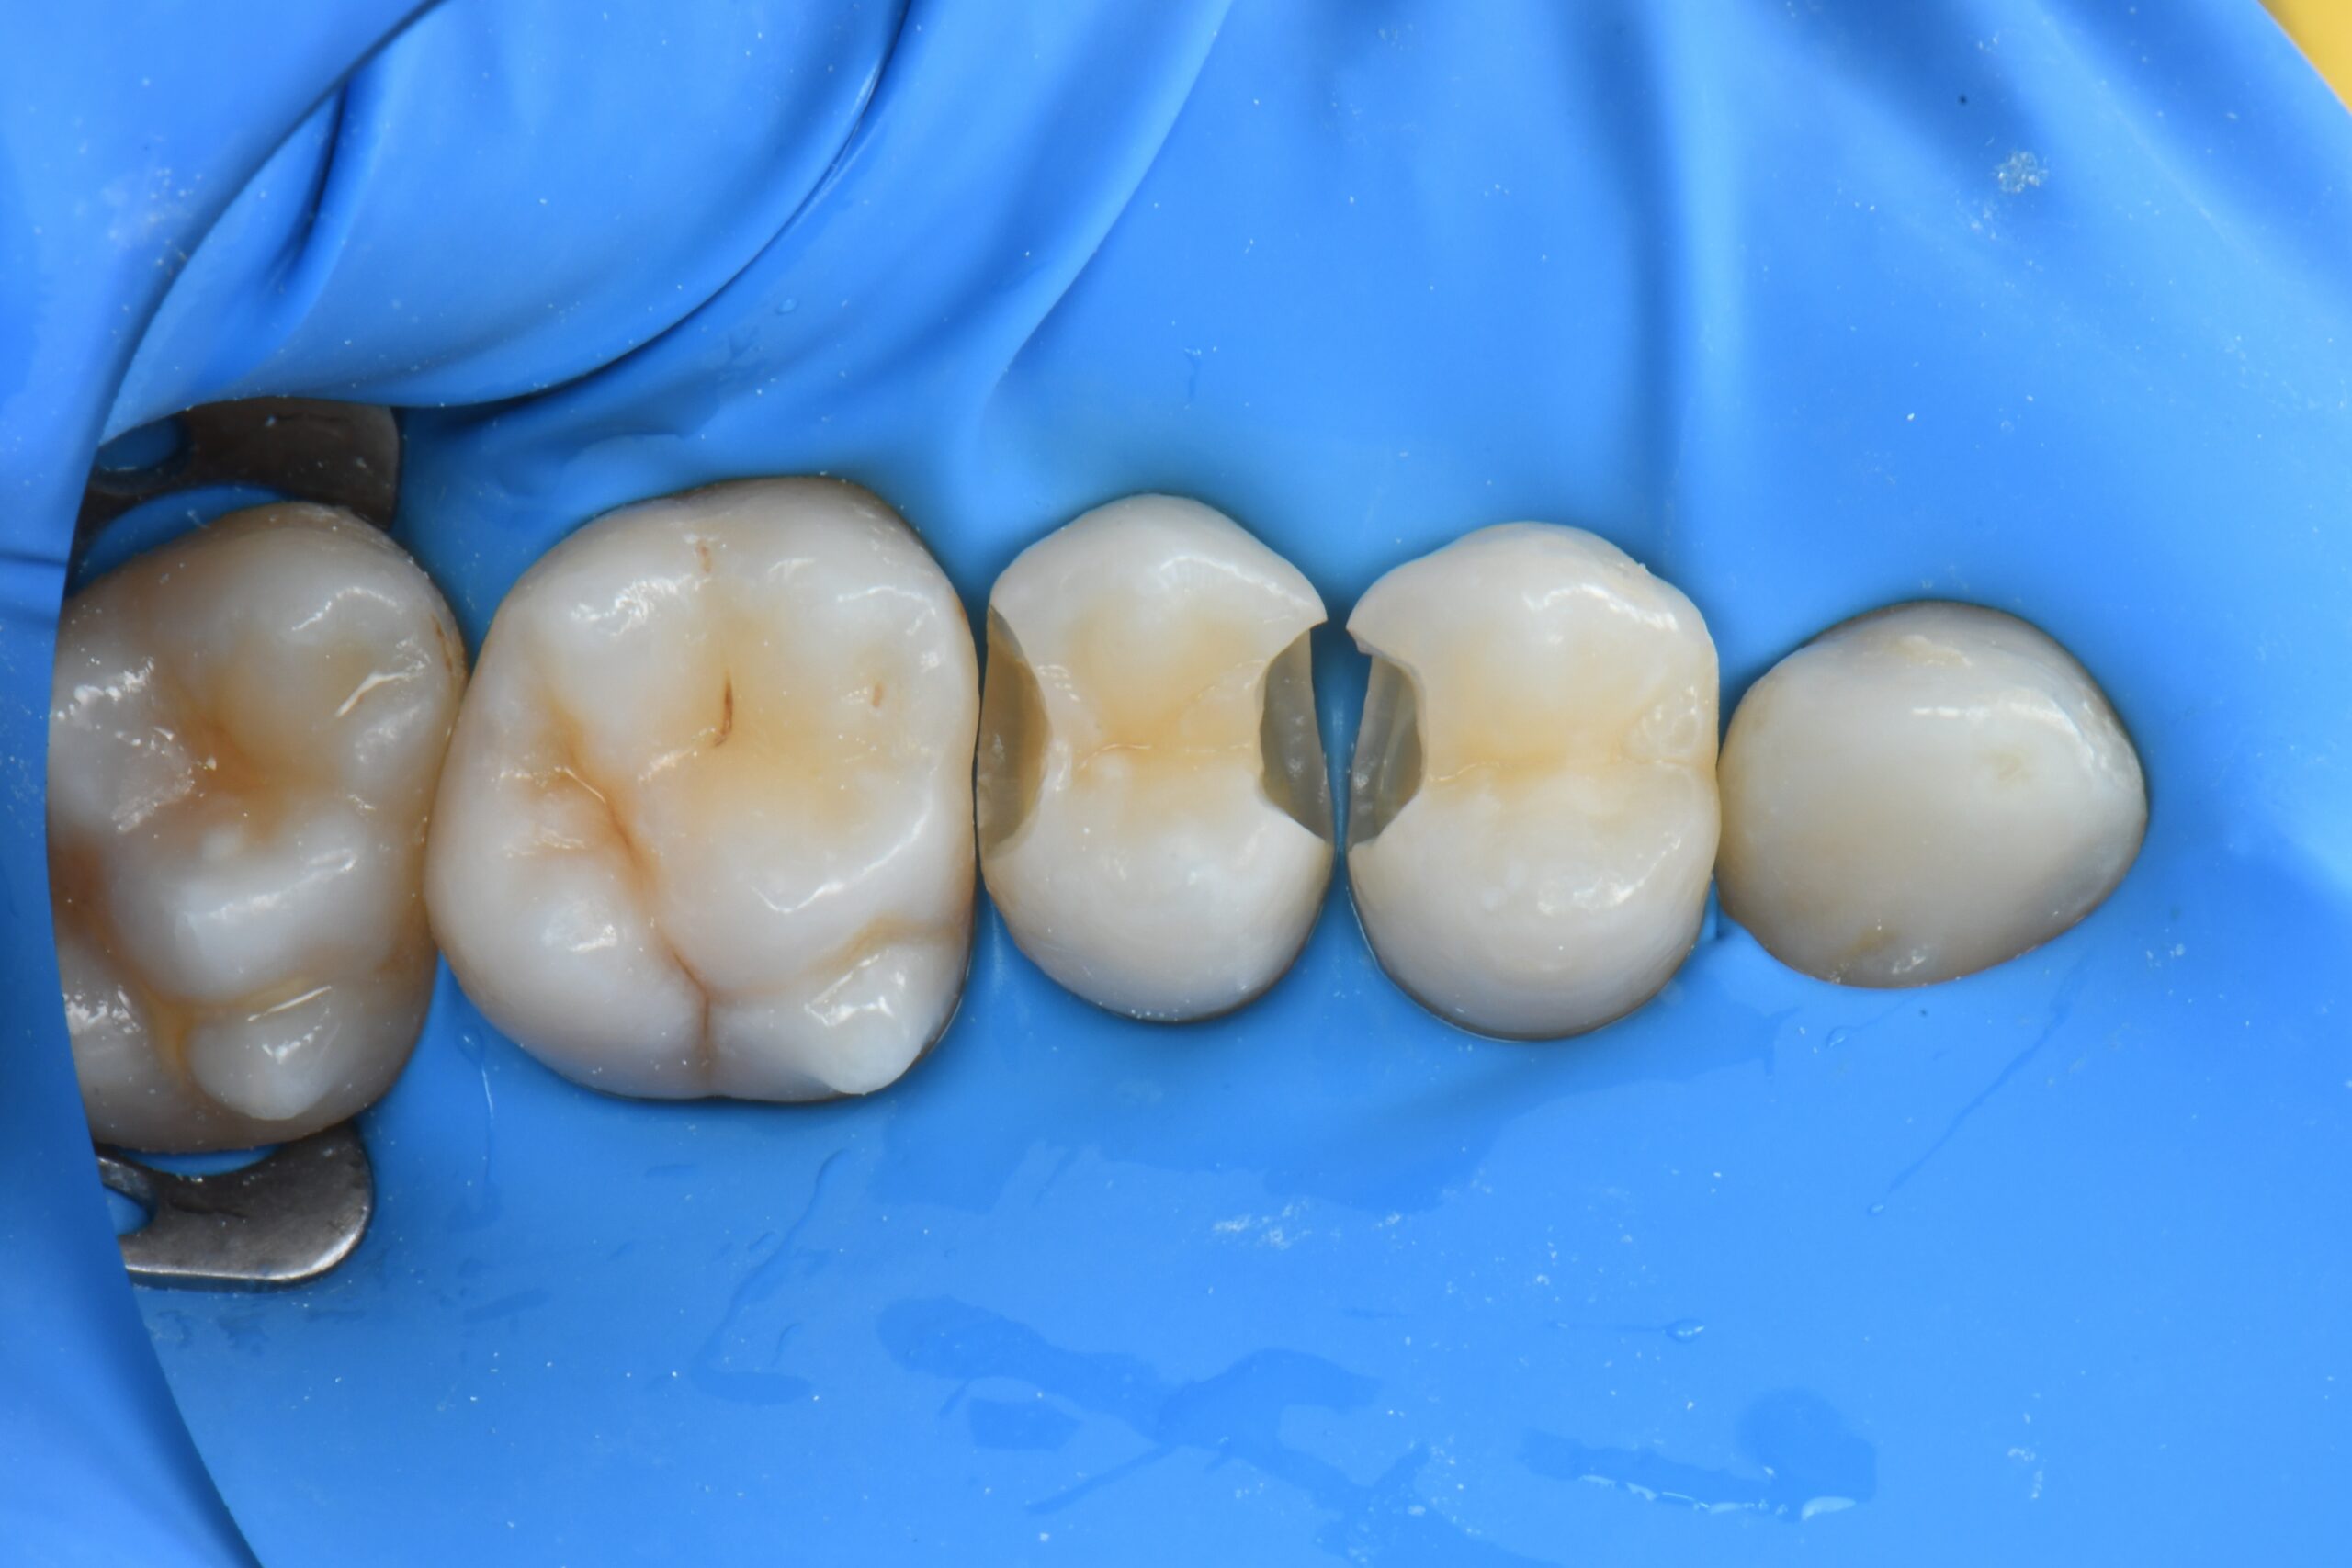

Close-up of four molar teeth isolated with a blue dental dam, two teeth have cavities prepared for fillings

Minimally invasive interproximal boxes are opened in order to remove the carious lesions.